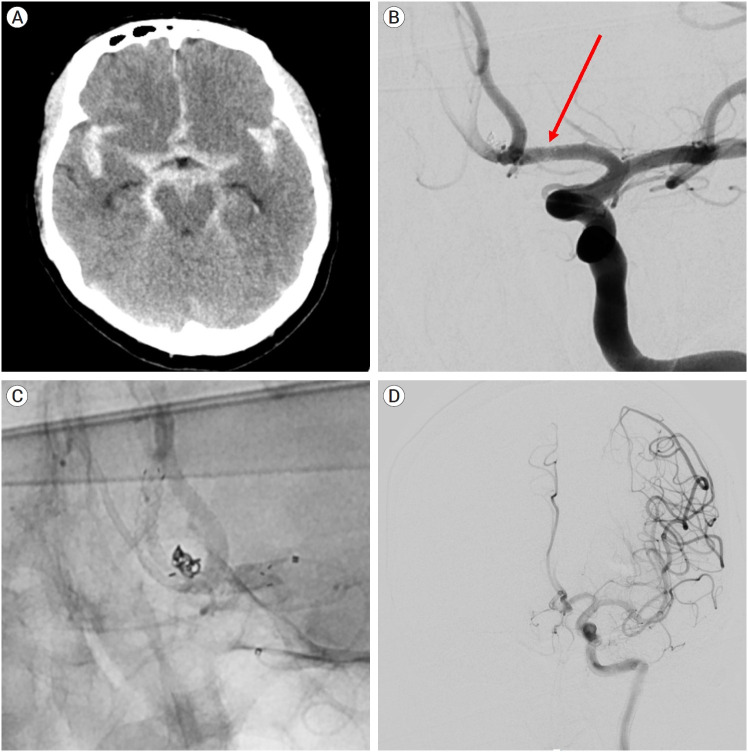

Objective: Stent-assisted coil embolization (SAC) is an effective method of treating intracranial aneurysms. The aim of the study was to assess the safety and efficacy of the new ACCERO stent for the treatment of cerebral aneurysms.

Methods: It was a retrospective, single-center study. Nine ruptured and 41 unruptured cerebral aneurysms were treated using the ACCERO stent between February 2021 and December 2023. Patient demographics, aneurysm characteristics, procedural parameters, grade of occlusion, complications, and clinical outcomes were analyzed. Follow-up was conducted with magnetic resonance angiography (MRA) or Digital subtraction angiography (DSA) was performed 6 to 12 months after the procedure.

Results: The ACCERO stent deployment was attempted in 51 cases, with replacement by the Neuroform Atlas stent in 1 case. Successful stent deployment was achieved in 50 cases, and appropriate wall apposition to the parent artery. The average clinical follow-up period was 17.1 months. Intimal hyperplasia was observed in 1 case, but no other clinical complications related to the stent occurred. Favorable clinical outcomes were observed in 92% of patients (46/50), including those with subarachnoid hemorrhage. Immediate favorable angiographic outcomes and complete occlusion were achieved in 90% (45/50) and 74% (37/50) of cases, respectively. Among the 45 patients who had imaging follow-up, favorable angiographic outcomes and complete occlusion were observed in 93.3% (43/45) and 82.2% (37/45) of cases, respectively.

Conclusions: The ACCERO stent is a braided-type stent that requires more attention than stents, such as the Neuroform Atlas or Enterprise stents. However, since the struts of the stent are fully visible, it can be more useful in treating challenging aneurysms once the user becomes familiar with its use.